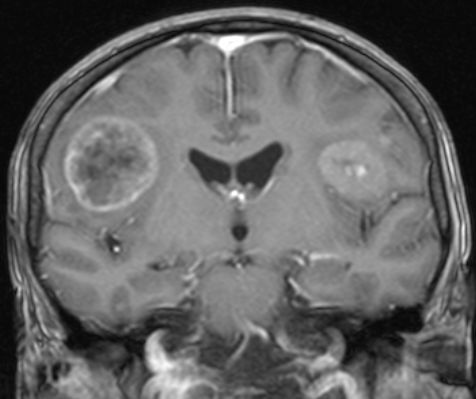

| MRT: multiple Hirnmetastasen | Adenokarzinom der Lunge. MRT-Untersuchung des Hirns. | |||